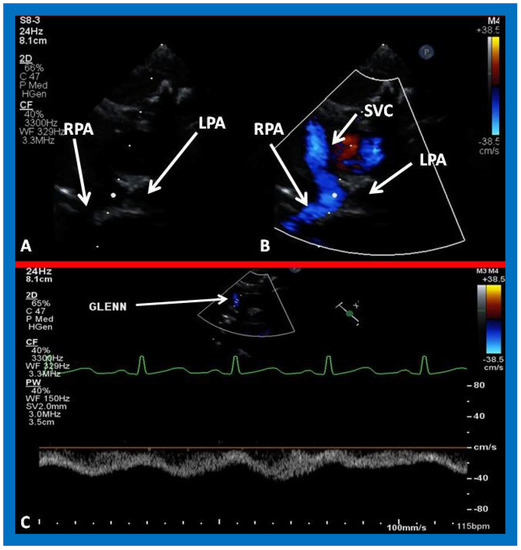

In patients who had banding of the PA, echo-Doppler studies should be scrutinized to demonstrate the banded PA diameter (Figure 22A,B and Figure 23A) and peak Doppler flow velocity across the banded PA (Figure 22C and Figure 23B); high Doppler velocity across the band (Figure 22C and Figure 23B) would suggest effective palliation. Low gradients and ineffective control of CHF may require tightening of the band; echo-Doppler evaluation is useful in making such an assessment.

Figure 22. Selected echocardiographic video frames demonstrating pulmonary artery band (PAB) with narrow diameter of 2.9 mm by 2D (A) and by color flow (B) and a high gradient (81 mmHg) by continuous wave Doppler (C) are shown.

Applsci 11 09472 g022